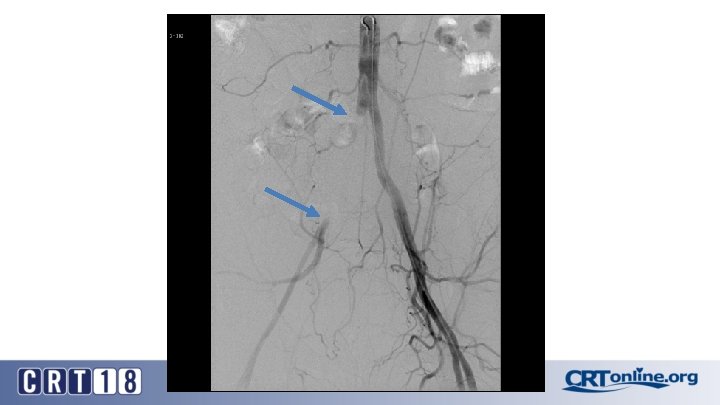

Blue Toe Syndrome

Returns Next day

Failed recanalization: BKA